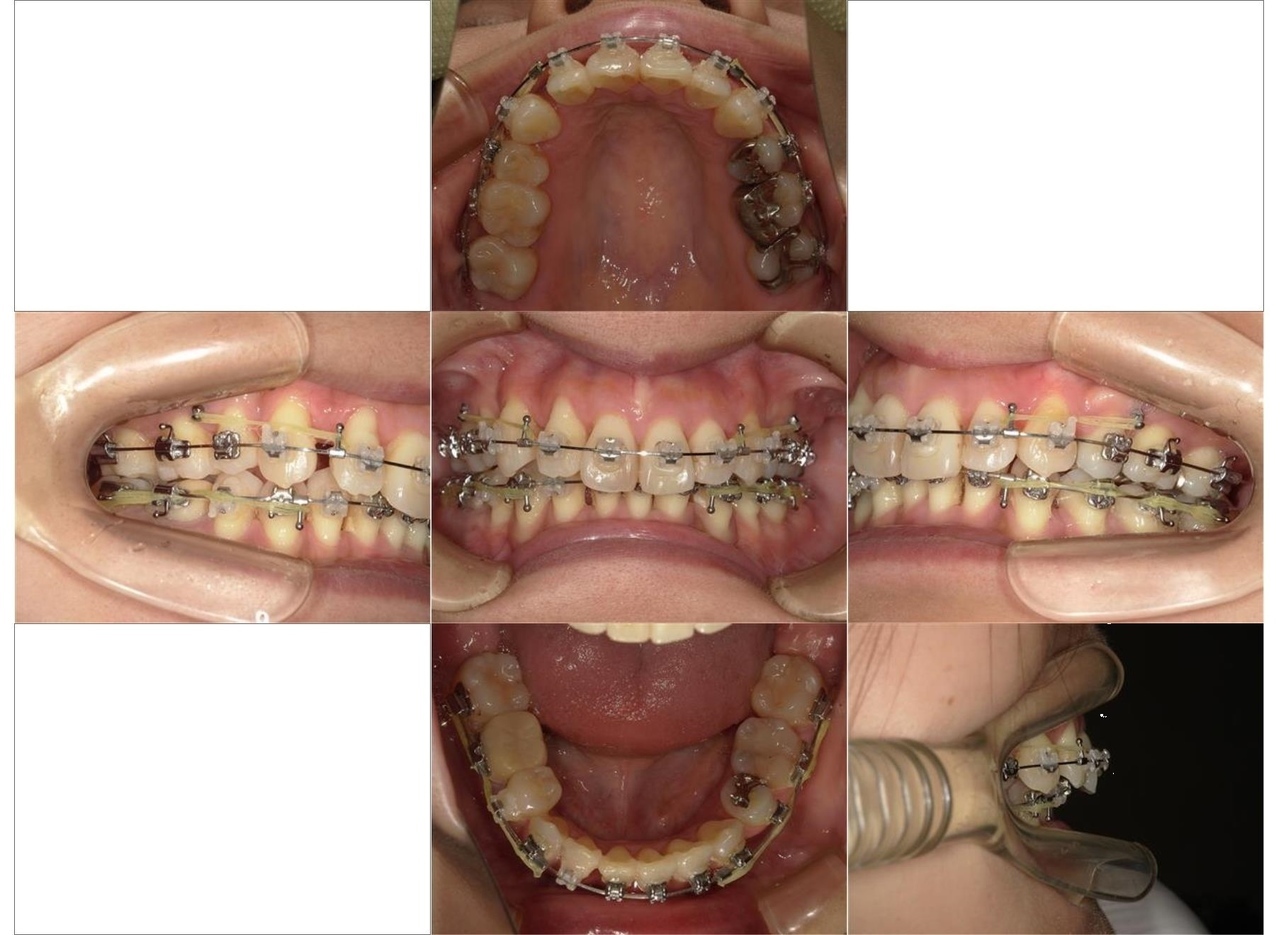

歯ならびの治療を主訴にご来院されました。上顎前歯の突出がみられ、唇が閉じにくく、麺類が食べにくいとのことでした。まず、保険診療で歯周病の治療を行いました。ワイヤー矯正とインビザラインによる矯正治療を説明し、ワイヤー矯正治療を希望されました。まず、歯を並べるためのスペースを確保するため、上顎小臼歯の抜歯を行いました。その後は、レベリング、リトラクション、正中合わせ、コントラクション、アイデアルアーチによる最終調整をしました(専門用語ですみません)術後は、食べ物が食べやすくなったこと、見た目が改善されたことを喜ばれていました。全体的に歯周病の進行が見られるため、今後は歯周病安定期治療による定期的な治療を続けていきます

マルチブラケットを用いたワイヤー矯正治療